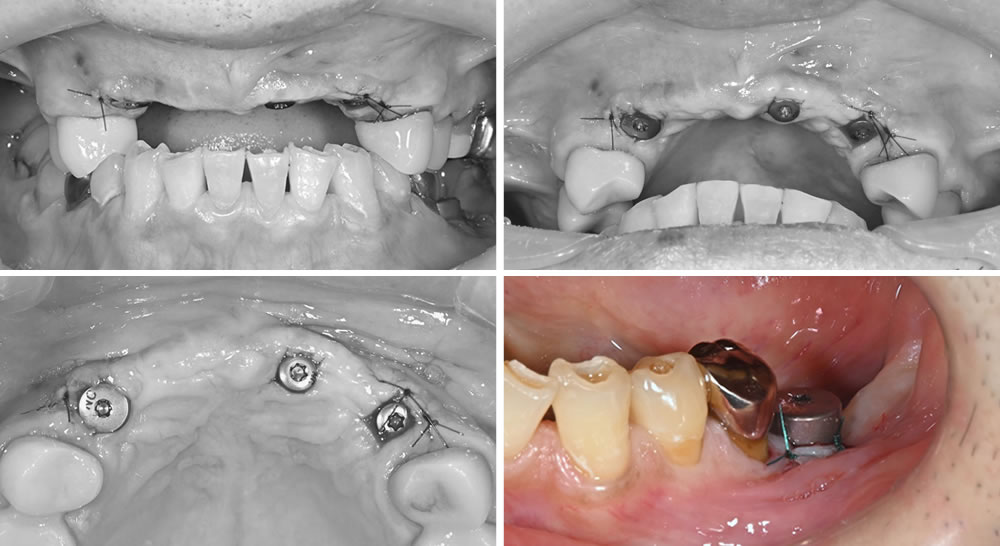

こちらの患者さまは、上顎前歯部分の差し歯が取れたとのことで初診来院されました。右下の写真からもわかるように、補綴物が広範囲にわたって脱離していることが確認できます。

上顎前歯は保存が困難であったため抜歯を行い、前歯部分の治療に加えて全顎的な包括治療を行う方針となりました。上顎前歯部にはインプラント治療を計画し、サージカルガイドを用いてインプラント埋入手術を実施していきます。

歯肉を剥離し、インプラントを埋入した状態です。設計されたサージカルガイドとズレが生じないよう、精密な処置を行いました。

唇側の骨が不足していたため、インプラントの埋入と同時に人工骨を用いて骨補填を行っています。

ナイロンの糸を用いて縫合、閉創を行いました。

上顎前歯部分と同時に左下奥歯にもインプラントを1本埋入し、縫合、閉創を行いました。